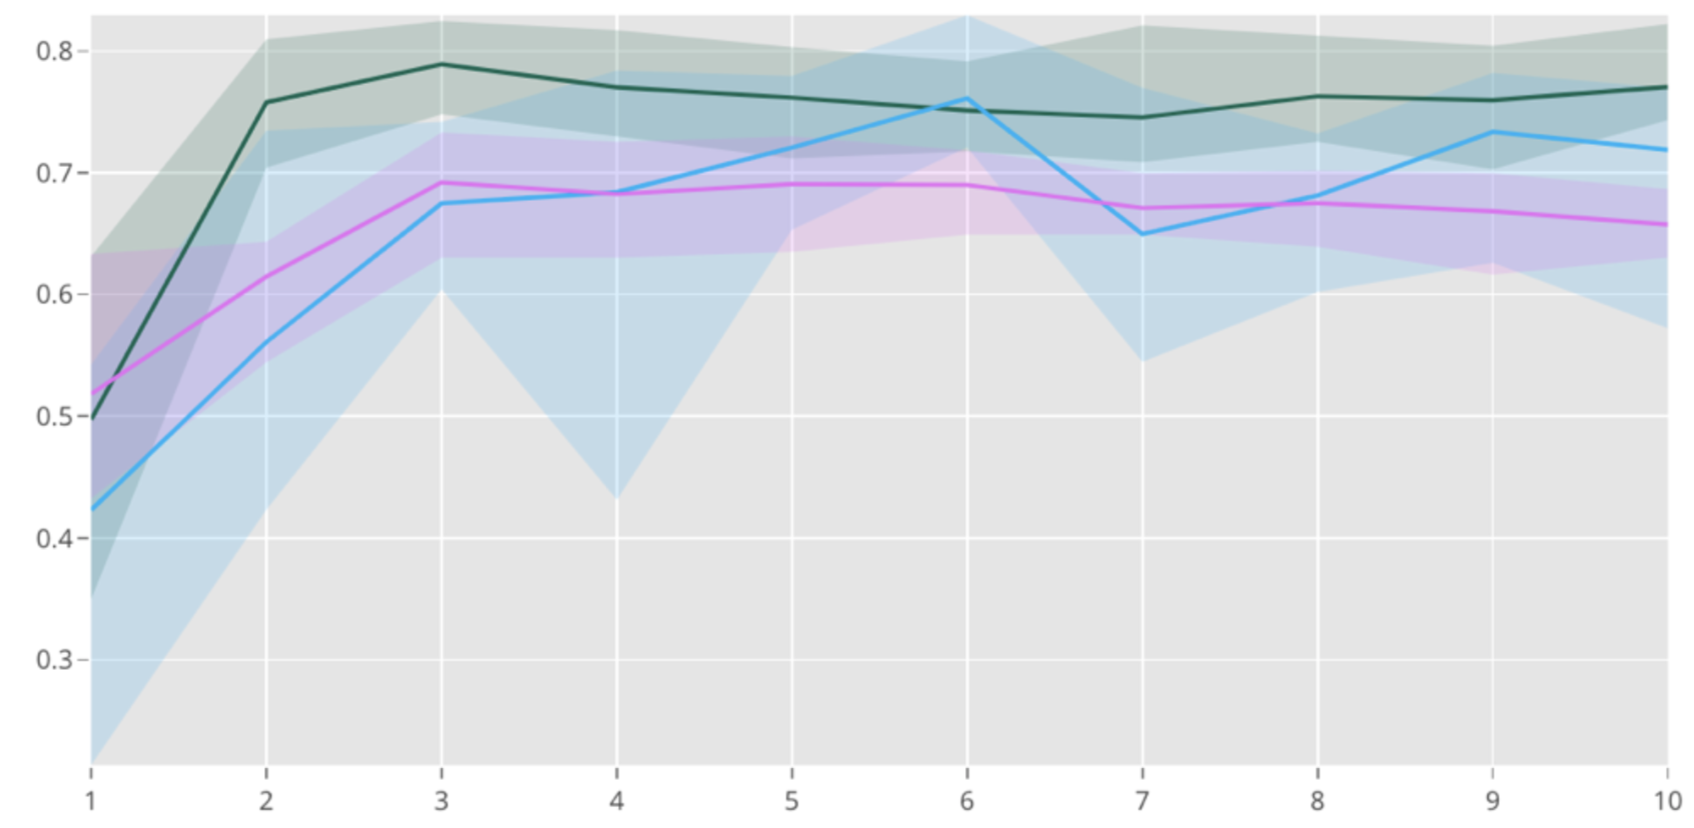

The multimodal on average improves accuracy efficiently by 4% and 7% compared to the baseline models which are an individual text model and an image model when fine tuned with learning rate . As show in Figure 5, shows the performance of our multimodal compared to two baseline models which are individual text model and image model on Indiana University dataset tuned with a learning rate of . The lines represent the mean accuracy and the spread represents the variance over the course of 10 stratified splits and 10 epochs. The bottom graph shows accuracy after tuning with a learning rate of . This yields a total dominance of the multimodal over the course of 50 epochs.

The experiments of over 10 stratified splits of the data yielded the following average results for multimodal and its stand alone submodals with high learning rates over 10 epochs. The low learning rate experiments were done with 3 stratified splits over 50 epochs.